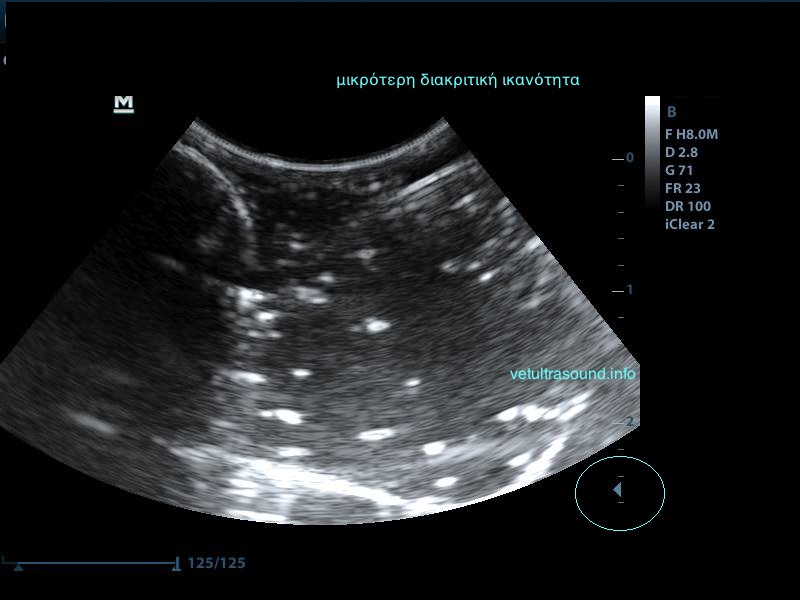

Σημαντικό ρόλο επίσης παίζει η κλίση της βελόνας σε σχέση με τον ηχοβολέα ( κεφαλή ), όσο πιο κάθετη είναι η βελόνα με τον ηχοβολέα τόσο καλύτερη εικόνα της βελόνας έχουμε, όσο αυξάνεται η κλίση τόσο μειώνεται η διακριτική μας ικανότητα.

Λόγω της κλίσης βλέπουμε μόνο την μύτη της βελόνας.